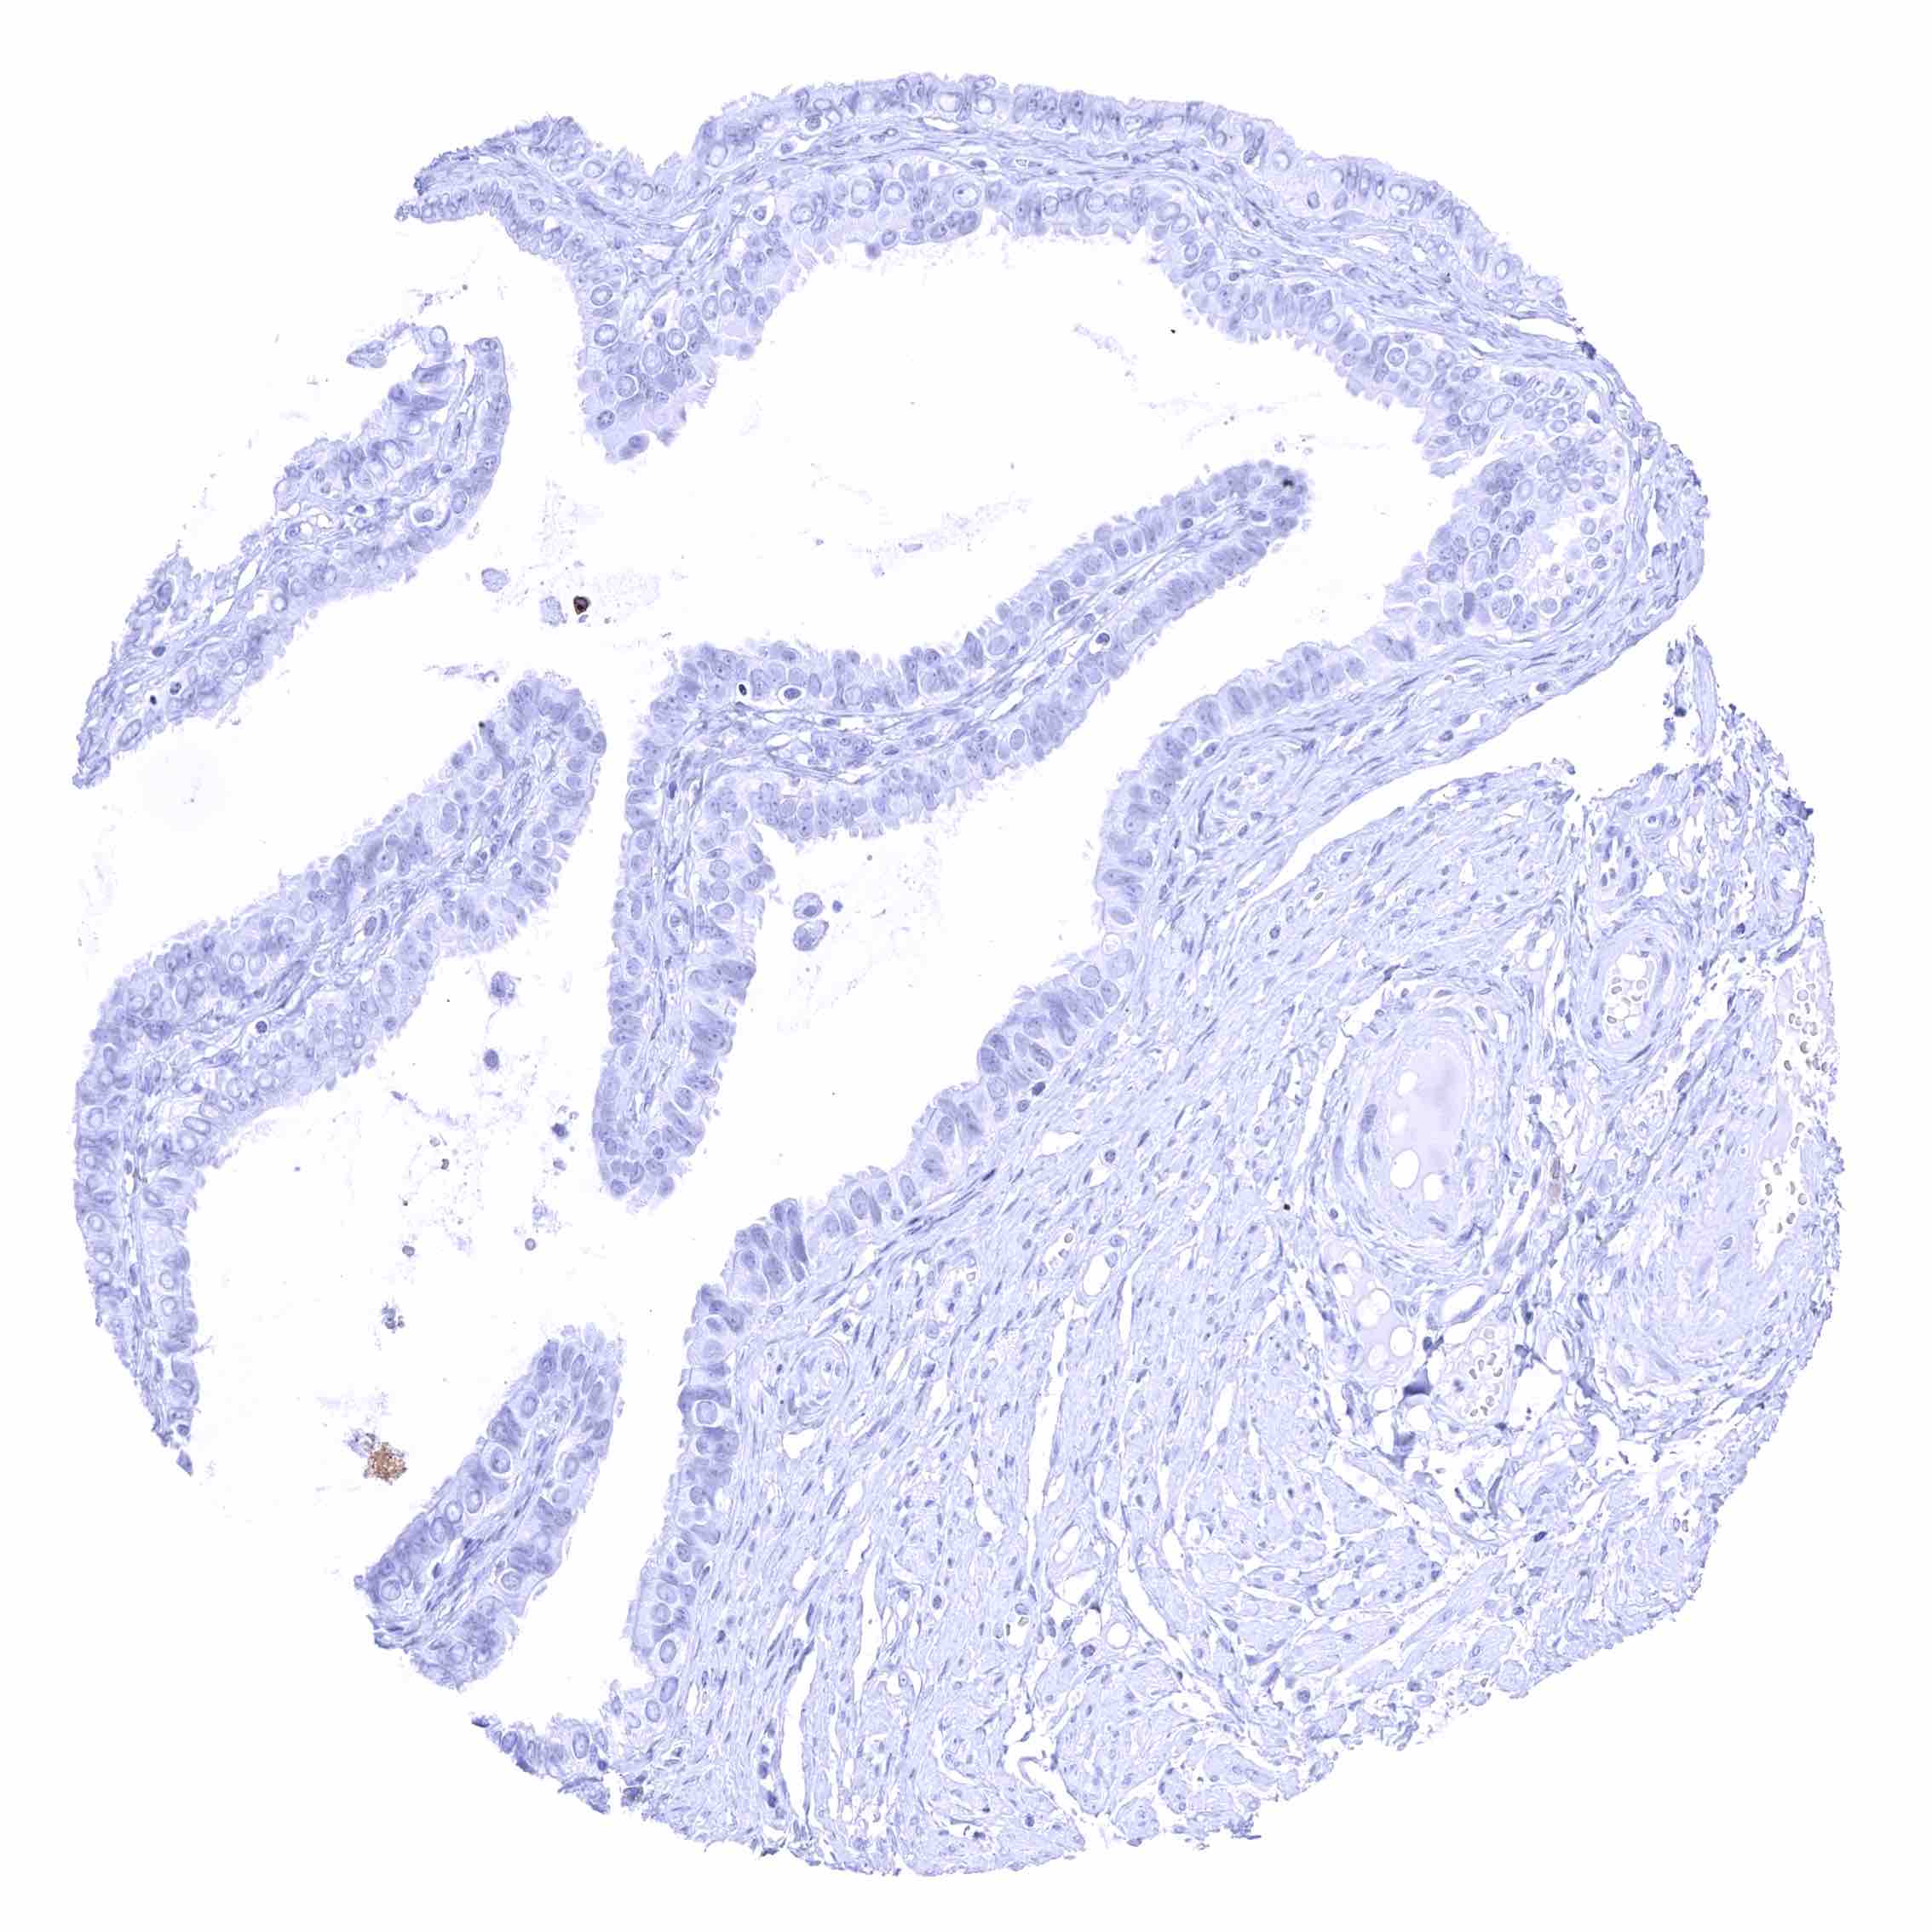

Uterus, endocervix.jpeg

Uterus, endometrium (pregnancy)

Uterus, endometrium (proliferation)

Uterus, endometrium (secretion)